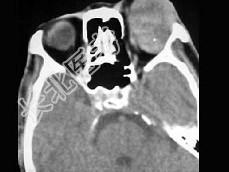

- 单项选择题男,45岁, 左眼疼痛伴视力下降一个多月,左眼明显外突, CT扫描如图所示,最可能的诊断是 ( )

A、左侧眶内炎性假瘤

B、左眶内血管瘤

C、左眶内纤维瘤

D、左眶内结核

E、左眶内转移瘤